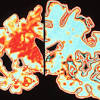

Alzheimer's researchers win brain prize Four dementia scientists have shared this year's 1m Euro brain prize for pivotal work that has changed our understanding of Alzheimer's disease.